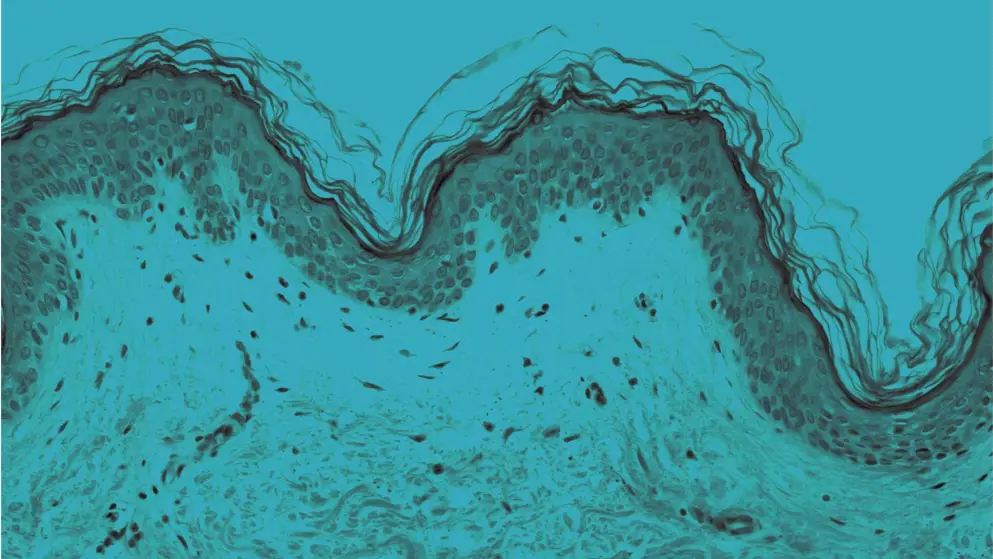

Atopic dermatitis (AD), commonly known as eczema, is a widespread autoimmune skin disease. Typical symptoms include skin irritation, redness, and bleeding. AD is marked by elevated levels of skin eosinophils, neutrophils, and mast cells, lymphocyte infiltration, and increased immunoglobulin E levels.

The exact cause of AD remains unknown. However, gene mutations, issues with the immune system, and contact with specific environmental factors play a role in changes to the skin barrier, contributing to the disease.